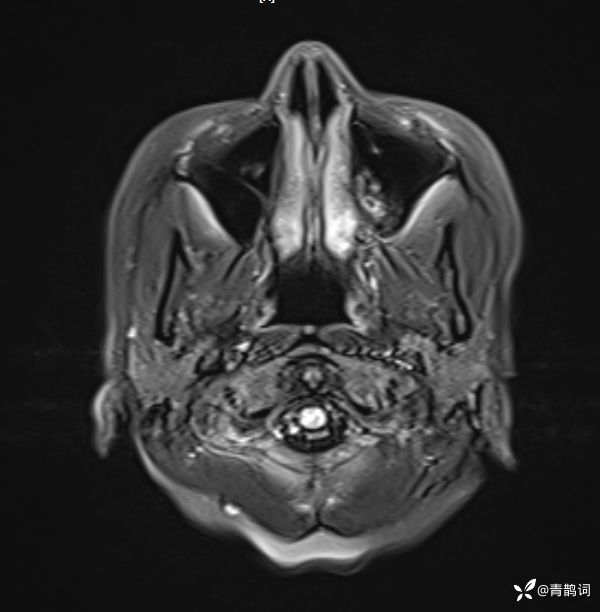

入院后完善磁共振:

T1: